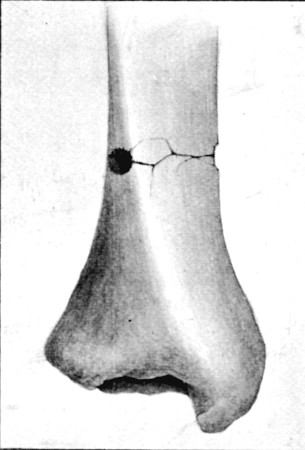

51. Lower End of Fractured Femur164

57. Tunnel Fracture at Surface of Tibia 219